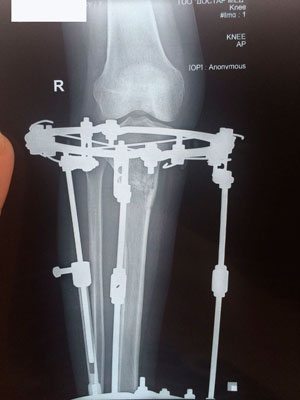

Исходник - 34 года.

Дата операции 29.09.2017г.

Дата снятия аппаратов 27.12.2017г.

Срок лечения 88 дней.